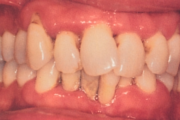

- igemepiir on taandunud (3)

- hamba kinnitussidemete kadu (3)

- igemealune hambakivi (4)

- vahed hammaste vahel (5)